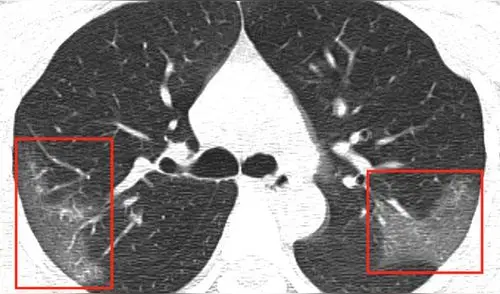

Evolución de las manchas en los pulmones después de tres días. Imagen: First Hospital of Lanzhou University.

En la primera radiografía, los médicos detectaron unas manchas blancas en la esquina inferior de los pulmones de la paciente, que se mantiene en el anonimato. Los expertos comparan la tonalidad de las manchas con la “opacidad de vidrio esmerilado”.

Sin embargo, las manchas se extendían hasta los bordes de los pulmones de la mujer, lo que antes también se había detectado en los infectados por coronavirus como el SARS y MERS.

Luego de tres días de tratamiento, los médicos realizaron nuevas radiografías para descartar un caso de neumonía común. Al ver las imágenes, se percataron de que las manchas blancas eran más notorias y extensas.